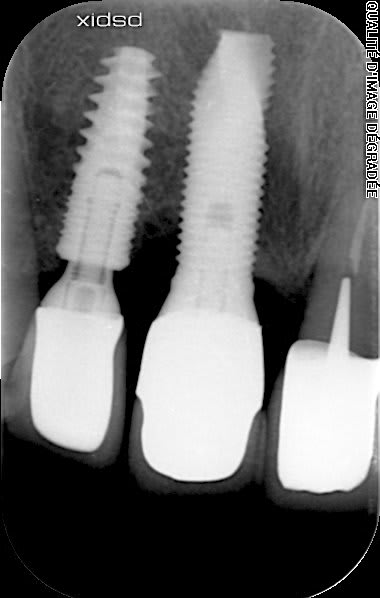

avez vous une idée pour l'implant central??

posé dans les année 1990.

dommage on voit pas la connexion.....mais je parierais bien sur un spline....(fiabilité 70%)

https://whatimplantisthat.com/implants/details/spline-twist-calcitek